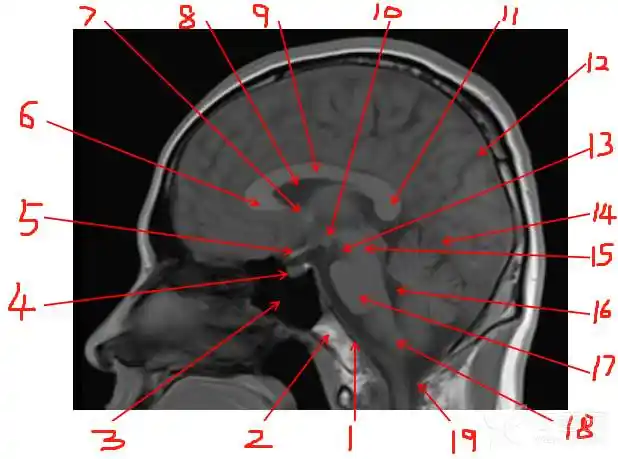

面神经解剖及常见病变影像诊断

磁共振检查如3d-tof-mra,fiesta等,有助于明确责任血管和面神经之间的

面神经瘤的影像学特点

面神经解剖及相关病变